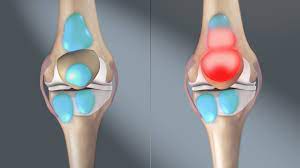

- 관절 부어오름: 관절이 부어오르거나 따뜻해지는 증상이 있을 수 있어요.

- 팽만 및 충혈: 관절 주위의 피부가 붉어지거나 붓는 증상이 있을 수 있어요.

급성 감염성 관절염

보통 증상은 몇 시간에서 며칠에 걸쳐 시작됩니다. 감염된 관절은 보통 심한 통증을 수반하고 때때로 불그스름하고 따뜻합니다. 이를 움직이거나 만지면 매우 아픕니다. 감염된 관절에 액체가 축적되어, 부기와 뻣뻣함을 야기합니다. 때때로 열, 오한이 증상으로 나타납니다. 매우 드물게 패혈성 쇼크가 발생합니다.